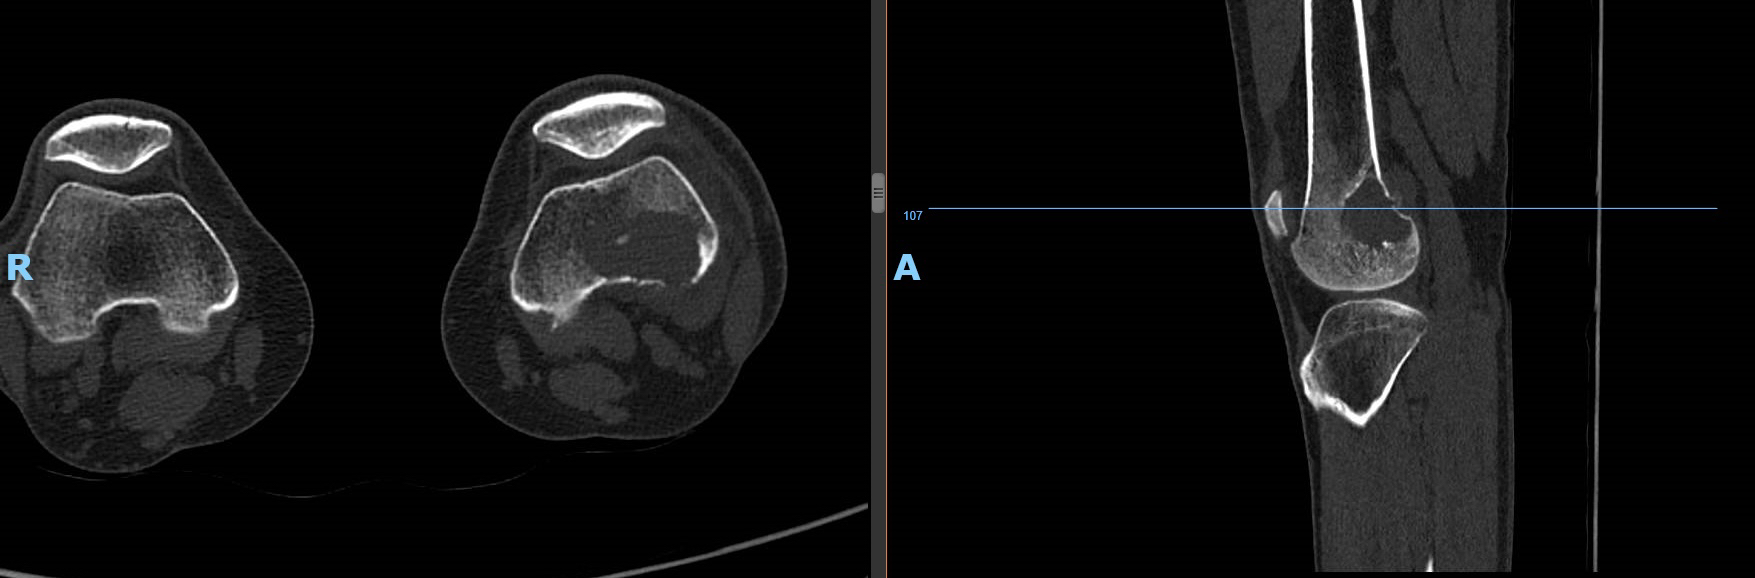

CT和 MRI,在骨肿瘤的诊断和定位方面是有意义的。对于非常小的骨皮质病变,例如骨样骨瘤,薄层 CT扫描可能是显示病变的最好方式,通过显示髓腔和皮质骨的形态,在理解局部骨骼的细微结构方面可以达到最佳效果。